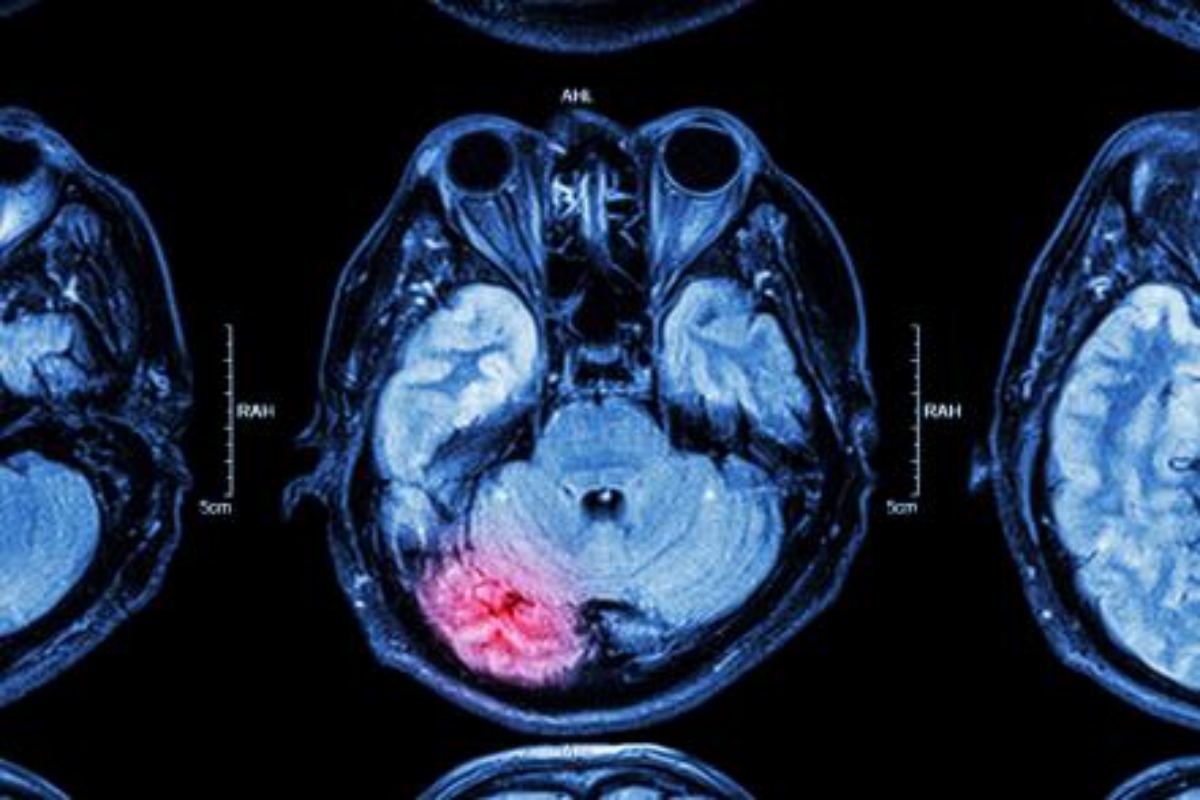

Az agyvelőgyulladás (encephalitis) az agy akut gyulladása, amit leggyakrabban vírusfertőzés okoz.

Az esetek jelentős részében a kullancsencephalitis-vírus és a herpeszvírus a betegség oka. Agyvelőgyulladás egyes belgyógyászati betegségek kapcsán is létrejöhet, azonban a fertőző (ezen belül főleg vírusos) eredet dominál. Némely vírus közvetlenül károsítja az idegrendszert (pl. az említett kullancsencephalitis, herpesz, mumpsz, járványos gyermekbénulás, Nyugat-Nílusi vírus, HIV). Más vírusok az immunrendszer aktiválódását követően képződő antitestekkel, másodlagosan okoznak kárt az idegekben (pl. kanyaró, rózsahimlő, bárányhimlő vírusai).